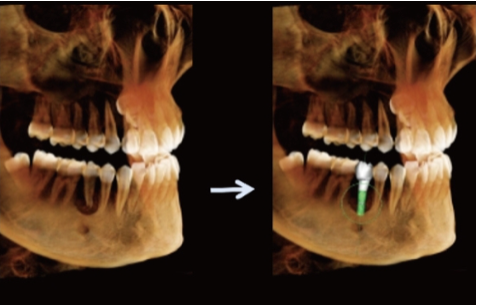

Planeamento Virtual de Implantes

Permite a simulação de procedimentos de implantes (implante + pilar + coroa), ajudando a selecionar o implante mais adequado.

Fornece alertas de proximidade ao canal nervoso, aumentando a segurança cirúrgica.

Facilita a comunicação entre médico e paciente, permitindo ao paciente visualizar claramente o procedimento de implante planeado.